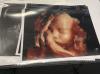

Я делала 3д узи в клинике "Медок Кожухово" у доктора Литвинова Д.О.

Стоимость УЗИ 3Д/4Д в этой клинике 5000₽. Провели полноценное скрининговое УЗИ, включая диагностику состояния плода, органов малого таза. И также врач делает объемные снимки и видео. После приема сразу выдается протокол УЗИ, флешку с фото и видео

Прием длился чуть больше часа 😍